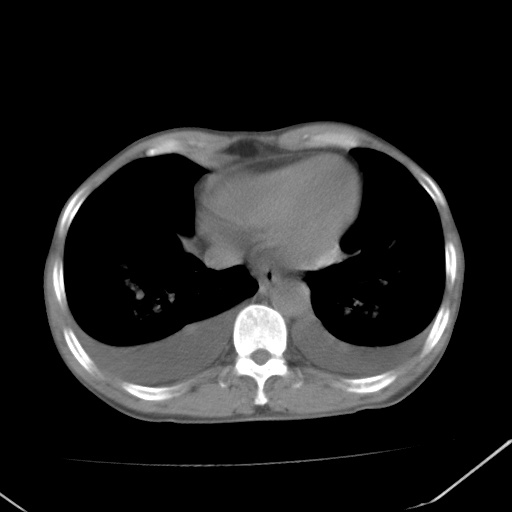

双肺野对称性磨玻璃影,分布于内中带,双侧胸水,患者有咯血。

左心房增大,考虑心衰,肺水肿。

双肺野广泛对称性磨玻璃影、实变影,以肺门为中心,主要分布于内中带,符合典型肺泡性肺水肿;伴双侧胸腔少量游离积液。结合患者既往病史且咯血就诊,支持多因素(尿毒症等)所致之肺水肿、肺出血、胸水;影像表现暂不考虑心源性水肿,且症状也不太符。需密切随诊结合临床治疗等进一步明确。

心影增大密度略低,双肺磨玻璃样高密度影及双侧胸腔积液,考虑心功能不全继发双肺肺水肿及双侧胸腔积液。心影密度略低,考虑贫血所致。